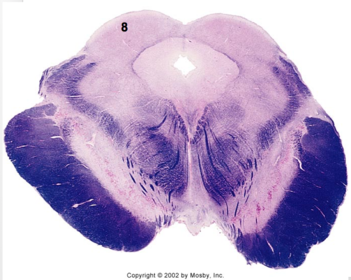

| Hypoglossal nucleus | |

| Hypoglossal nerve | |

| Dorsal motor nucleus of X | |

| Nucleus ambiguus | |

| Solitary tract | |

| Solitary nucleus | |

| ALS | |

| Medial lemniscus | |

| Medial longitudinal fasciculus | |

| Spinal tract of V | |

| Spinal nucleus of V | |

| Lateral (external, accessory) cuneate nucleus | |

| Medullary pyramids | |

| Anterior spinocerebellar tract | |